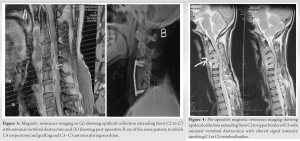

Atlantoaxial interval was maintained. Based on the MRI, provisional diagnosis of Pott’s disease was made. Because of the patient’s precarious neurologic state, it was decided to decompress the cervical cord immediately. Anterior Smith Robinson approach was taken. C3 corpectomy and decompression by the above mentioned method followed by anterior grafting and plating from C2 to C4 (Anterior Cervical Discectomy and Fusion) was done (Fig. 2c). CBNAAT and biopsy came out to be positive and ATT was started to be continued for 18 months. On follow-up at 6 weeks, ESR was 74, hand grip had improved and power at wrist, elbow, and shoulder was 3/5. At 3 months, ESR was 54, power at wrist, elbow and shoulder was 4/5. At 6 months, ESR was 18 and power at wrist, elbow and shoulder was 4+. Cervical spine X-ray film showed evidence of graft fusion with no loss of height (Fig. 2c). At the end of 1 year follow-up, the patient had fully recovered motor function with power at wrist, elbow, and shoulder being 5/5 and remained so in bilateral upper limb. In another case, a 46-year-old male came with neck pain and weakness bilateral upper limbs for 2 weeks which was gradually increasing. He was non-diabetic and non-immunocompromised. However, he had a history of chronic alcoholism. There was a history of multiple falls in the past 4 months. The patient was already on ATT since last 20 days. On examination, power in bilateral shoulder was 2/5, while that in bilateral elbow and wrist was 3/5. Power was 5/5 in bilateral lower limbs. MRI showed involvement of C3 to C7 vertebral bodies with anterior epidural collection extending from C2 to C7 causing spinal canal stenosis and compression of the exiting nerve roots (Fig. 3a).

However, there was no significant vertebral body destruction as height of body was maintained. Atlantoaxial joint space was normal. In March 2021, the patient underwent C4 corpectomy and decompression followed by anterior grafting and plating from C3 to C5 (ACDF) (Fig. 3b). ATT was started after the CBNAAT report. The patient had improved power in bilateral arm at 6-week follow-up with power being 3/5 at bilateral shoulder and 4/5 at elbow and wrist. On follow-up 3 month later, ESR was 56 and power at wrist, elbow and shoulder was 4/5. At 6 months after surgery, ESR was 16, and the patient had fully recovered motor function with power at wrist, elbow, and shoulder being 5/5 and remained so in bilateral upper limb. At 6 months, cervical spine X-ray film showed evidence of graft fusion with no loss of height. The patient is still under follow-up and on ATT. In other case, a 31-year-old male presented with neck pain and weakness in bilateral upper limbs of 2-month duration. The patient was HIV positive. Power was 2/5 at bilateral shoulder, elbow, and wrist with poor hand grip. History of fever, loss of appetite, and loss of weight was present. Another doctor who had advised ATT to the patient based on MRI which patient had been taking for the past 2 months; however, there was no improvement in symptoms. MRI showed epidural collection extending from C2 to upper border of C5 vertebra causing scalloping and compression of cord (Fig. 4). There was evidence of altered signal intensity involving C1 to C5 vertebral bodies but no vertebral body destruction (Fig. 4). In August 2021, the patient underwent C4 corpectomy and decompression by the same method, followed by anterior grafting and plating from C3 to C5 (ACDF). ATT was continued after the positive CBNAAT report. At 6-week follow-up, power had improved in bilateral arm with power being 3/5 at bilateral shoulder and 3/5 at elbow and wrist. On follow-up 3 months later, ESR was 47 and power at wrist, elbow, and shoulder was 4/5. At 6 months after surgery, ESR was 32 and patient had shown further improvement in motor power. At 9 months, ESR was 12 and motor power at wrist, elbow, and shoulder was 5/5 and remained so in bilateral upper limb. The patient continues to be under our follow-up and on ATT. In all three cases, we were able to decompress the cord and were able to remove all the collections and caseous material and also achieved spinal stabilization. All three patients had a gradual and complete recovery of motor power within 6 months to 1 year after surgery. There was no recurrence in this period. We had no major complications. Patients did have pain at the operative site postoperatively which gradually subsided. All three cases received ATT postoperatively. All three cases showed gradual healing on subsequent follow-ups based on plain radiographs and MRI done postoperatively showing good fusion of graft with the adjacent vertebrae. Overall patients are free of pain and made a good recovery in terms of neurological deficit. Patients are still under regular follow-up periodically with monthly LFT and ESR reports as patients are on ATT.